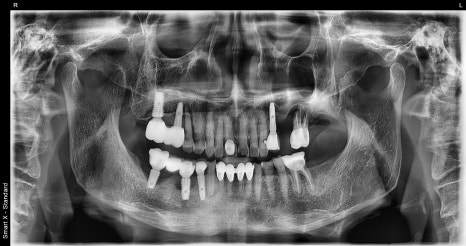

✅ 치료 전 사진

왼쪽 사진: 처음 내원하셨을 때 촬영한 파노라마 엑스레이입니다.

기존 임플란트 주변 어금니 여러 개에서 염증과 흔들림이 보였고, 전체적으로 저작 기능 저하와 심미적인 불편함이 있었습니다.